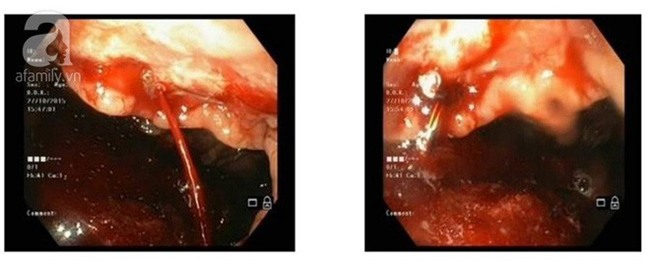

Xuất huyết do ung thư dạ dày.